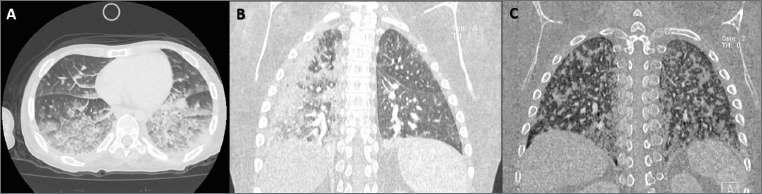

An 18-years-old non-ambulant male on daily steroids treatment since the age of four, with a history of delayed puberty, severe osteoporosis, and vertebral deformities. Following a car rear-end collision with no apparent injuries, the patient developed an acute anxious state accompanied by vertigo, vomiting and tachycardia, which rapidly progressed to cardiopulmonary shock and coma. He was initially admitted to a local Emergency Department (ED), where a femoral fracture was not suspected. Brain CT imaging was unremarkable, chest CT revealed bilateral cotton-like opacities, predominantly in the posterior-inferior regions, accompanied by interstitial congestion (Fig. 1-A). The patient was urgently transferred to our hospital in critical condition with respiratory and hemodynamic instability, requiring orotracheal intubation and ICU admission for advanced support due to acute left ventricular dysfunction. Although the rapid progression to multiorgan failure raised suspicion of acute myocarditis, cardiac MRI did not confirm this diagnosis. Given the patient’s history of a car accident, a lower limb X-ray was performed due to suspicion of fat embolism syndrome (FES), which confirmed the presence of a distal suprametaphyseal fracture of the right femur. The clinical suspicion was further supported by additional clinical and laboratory findings, including thrombocytopenia and anemia, which required red blood cell and plasma transfusions. Retinal hemorrhages were also noted, along with the gradual appearance of bilateral thalamocapsular lesions (Fig. 2). During a prolonged ICU stay, the patient was gradually weaned from mechanical ventilation. Neurological status progressively improved, ultimately resulting in full recovery of both motor and cognitive functions.

A 13-year-old non-ambulant male, on steroid therapy since the age of six and with no prior history of fractures, was referred to our ED following a fall from his wheelchair. He sustained distal metaphyseal fractures of both femurs and minor facial abrasions. A few hours after admission, the patient developed progressive respiratory worsening requiring non-invasive ventilation (NIV). Chest CT revealed bilateral areas of increased density with diffuse parenchymal consolidations (Fig. 1-B). Laboratory investigations showed moderate anemia and thrombocytopenia. The patient received supportive care, resulting in gradual clinical and radiological improvement, along with normalization of laboratory parameters. He was discharged in good general condition, although nocturnal NIV was continued as part of his long-term respiratory support regimen.

A 15-year-old non-ambulant boy with a history of steroid treatment since the age of seven was evaluated in our ED following simultaneous bilateral femoral fractures sustained from an accidental fall from his wheelchair. His medical history included mild restrictive respiratory disease, mild scoliosis, and reduced bone density, but no previous fractures. The patient was initially discharged with an indication for outpatient orthopedic follow-up. However, less than 48 hours later, he was re-admitted due to worsening respiratory function with tachypnea, low-grade fever, somnolence, tachycardia, and hypoxia. Laboratory exams detected hyponatremia. High-flow oxygen therapy, non-invasive ventilation, and intravenous diuretics were initiated. Due to persistent gas exchange impairment, helmet CPAP was started. Over the following days, as serum sodium levels normalized, the patient developed progressive anemia, requiring transfusion with packed red blood cells. A chest CT scan revealed bilateral, patchy, partially confluent pseudonodular consolidations, predominantly involving the posterior basal lung regions (Fig. 1-C). A diagnosis of fat embolism syndrome (FES) was made. The patient received supportive care and experienced a full clinical recovery, with normalization of both laboratory and radiological parameters within 6 days.

Figure 1. Each panel illustrates the characteristic Chest CT imaging pattern associated with Fat Embolism Syndrome in our case series. (A) Patient #1: diffuse, bilateral, symmetrical “cottony” alveolar opacities with posterior–inferior predominance and interstitial congestion. (B) Patient #2: bilateral areas of increased density, particularly in the right lung, with parenchymal consolidations in the right upper and lower lobes and smaller dependent consolidations in the left lung. (C) Patient #3: bilateral patchy, partially confluent pseudonodular consolidations, predominantly in the posterior basal regions.